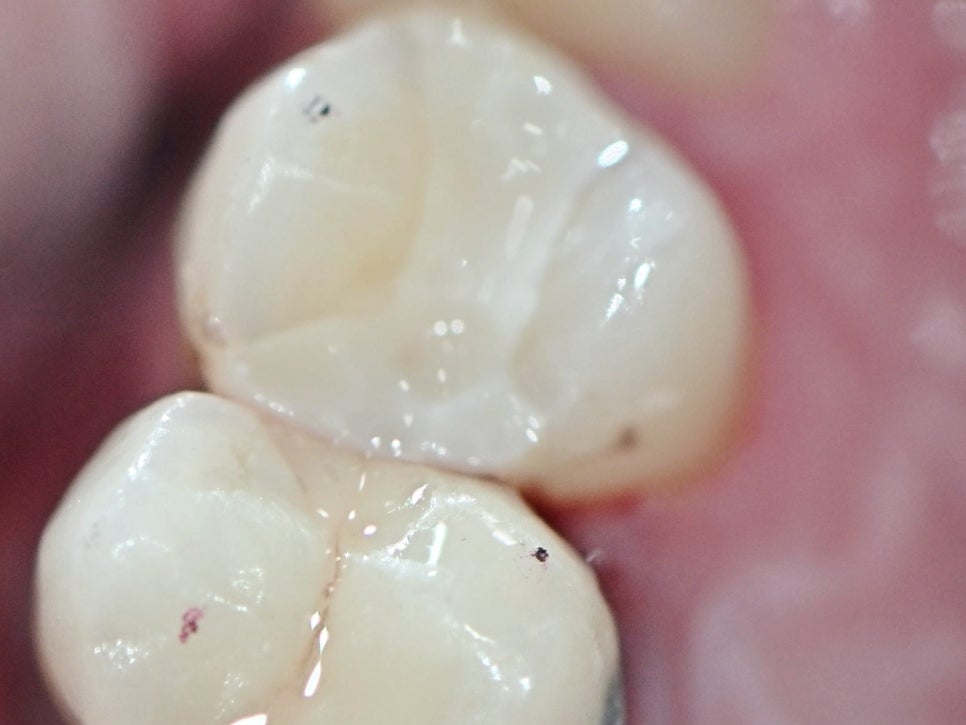

마곡동치과_인레이 보철물 제작 완료

마곡동치과_인레이 당일 부착 후 완성

정밀하게 완성된 인레이 보철물은 그날 바로, 그 자리에서 부착됩니다.

색상, 밀착도, 교합 상태까지 꼼꼼히 체크한 뒤 한 번의 내원으로 치료가 깔끔하게 종료됩니다.